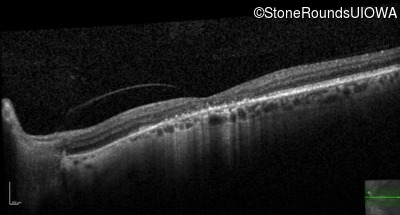

This 52 year old man had normal vision until his mid 30's when he began to have trouble distinguishing colors. the issuing 10 years he had a gradual loss of visual acuity accompanied by increasing photophobia.

| Age at visit: 61 years |

| Age at visit: 64 years |